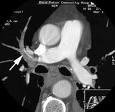

The time spent interpreting CT pulmonary angiographic studies is critical; death from an acute pulmonary embolism can occur in as little as one to two hours. The Effect of Teleradiology on Time to Interpretation for CT Pulmonary Angiographic Studies, by Scott Kennedy, M.D., et al., evaluates the results and implications of surveys completed by radiology administrators and emergency medicine physicians at Yale-New Haven Hospital. The surveys were used to establish target benchmarks for optimal interpretation time and to assess the impact of adding off-hours interpretation to current practice.

The authors reported that adding only 40 hours of teleradiology coverage per week decreased turn-around time for preliminary written reports, suggesting that teleradiology can help meet quality improvement standards and ensure timely diagnosis of time-critical illnesses.